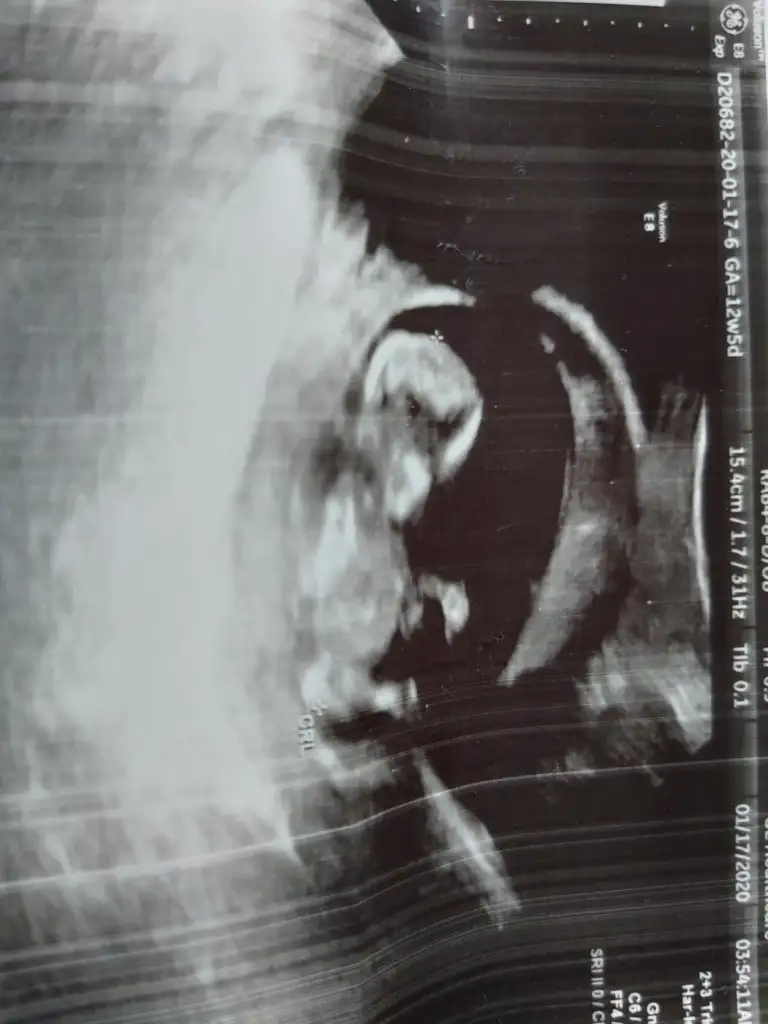

mrhaba lütfen yorumlarmisiniz sizce kızmı erkekmi bi arkadas icin soruyorum

Sevgili İkra,

Yorumlarsan çok sevinirim. ☺️❤️